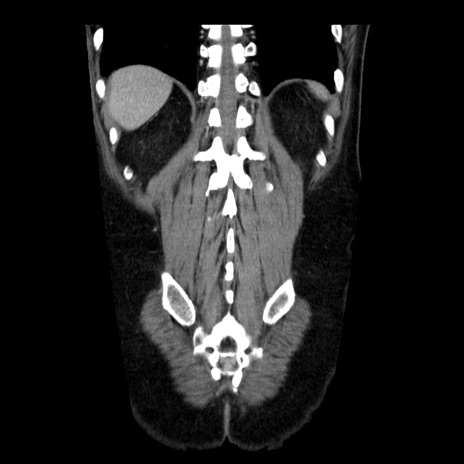

症例29(冠状断像)

【症例】40歳代男性

【現病歴】2日前から胃痛あり。徐々に周期的な激痛に変化した。本日になっても激痛があるため受診。

【身体所見】意識清明、BT 38-39℃台あり、腹部:膨満、やや硬、右下腹部に圧痛あり。

【データ】WBC 8500、CRP 23.26